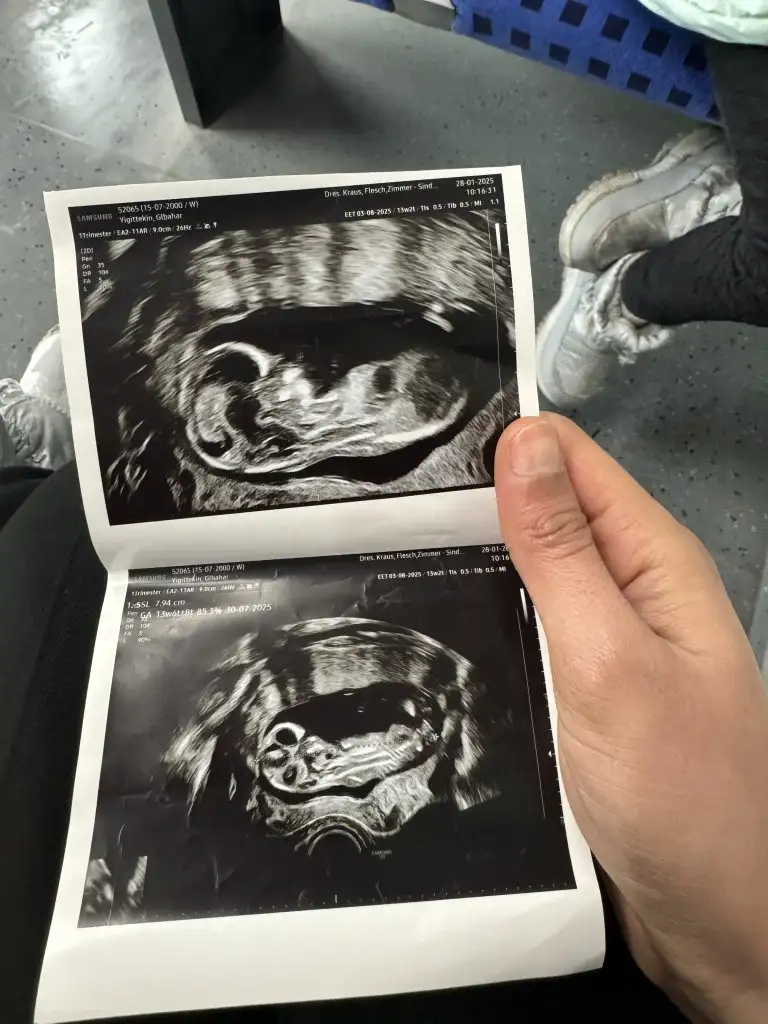

Kizlar bende az çok ramziden anlıyorum ama bu ultrason farklı geldi ultrason terimleri sol tarafta kalınca bebekte sagdamidir soldamidir çözemedim anlayan varsa cinsiyet tahmininde bulunabilirmi M meryem2132 Rica etsem sende bakarmisin kafam karıştı da benim